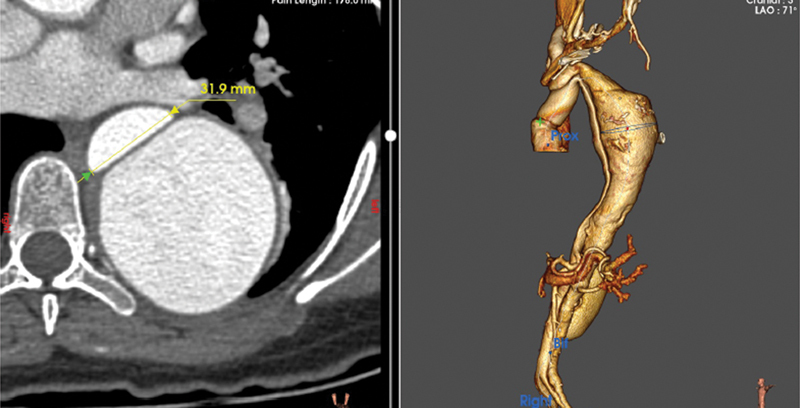

冷冻象鼻(FET)一直是治疗急性和慢性主动脉夹层的主要方法。尽管文献中报道了各种并发症,但据我们所知,血管内移植物导致胸降主动脉破裂的报道尚未发表。我们报告在先前的A型主动脉夹层导致胸降主动脉破裂的保留瓣根置换术后进行FET手术。

The frozen elephant trunk (FET) has been a mainstay in the treatment of acute as well as chronic aortic dissections. Although various complications have been reported in the literature, rupture of the descending thoracic aorta by the endovascular graft has, to our knowledge, not been published. We report an FET procedure following previous valve-sparing root replacement for Type A aortic dissection leading to rupture of the descending thoracic aorta.